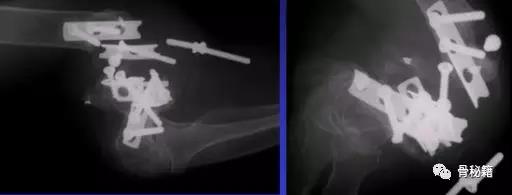

6、良好的固定需要两个板,平行or垂直?在肱骨远端骨折中,一块钢板通常不足以保证良好的稳定性,而在其他骨折(例如,胫骨近端和股骨远端)中,LCP的引入消除了对双柱固定的需要。应谨慎使用单侧钢板板,仅在单柱损伤的情况下可以应用。

7、钢板如何搭配?迄今为止,通常使用前两种钢板的固定。AO推荐在治疗中应用垂直钢板。然而,这种方法受到了广泛的批评 - 主要是因为通过后外侧板难以获得足够的螺钉数量和前后方向的长度的螺钉固定。与垂直钢板相比,平行板配置似乎提供了更好的生物力学性能。实在不行的时候再用三钢板技术

固定的八个细节:1、每个螺钉都应该经过钢板固定2、每个螺钉固定骨折块的螺钉,在他的对侧应该也有一个钢板的把持3、在远端一定要打满螺钉4、每个螺钉要尽可能的长5、每个螺钉需要尽量的对关节面的骨块进行固定6、螺钉应通过交叉锁定在一起,从而形成角稳定结构并将内外侧柱连接在一起7、钢板需要再髁间完成加压8、所使用的板必须足够坚固并且足够坚硬以抵抗在髁上水平处的断裂或弯曲。